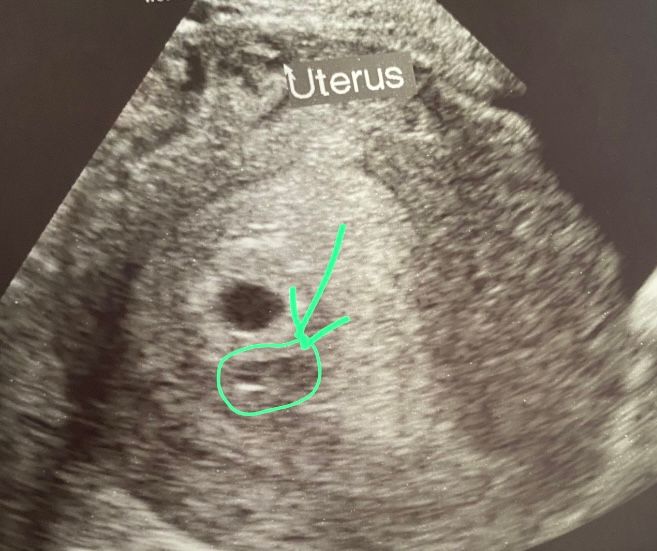

ксения в Клуб беременных 2 года Что это может быть? узи беременность до 5 недель узи до 6 недель Посмотрите еще 20 записей на эту тему Отменить Ответить Татьяна А доктор-узи никак не прокомментировал ? 30.06.2023 Ответить ксения Татьяна, нет а я обратила внимания уже уйдя от врача 30.06.2023 Ответить Хочу родить уже 🙃 Низкий уровень b-ХГЧ Чаты Беременных Выберите чат: Январята-2026 Февралята-2026 Мартята-2026 Апрелята-2026 Майчата-2026 Июнята-2026 Июлята-2026 Августята-2026